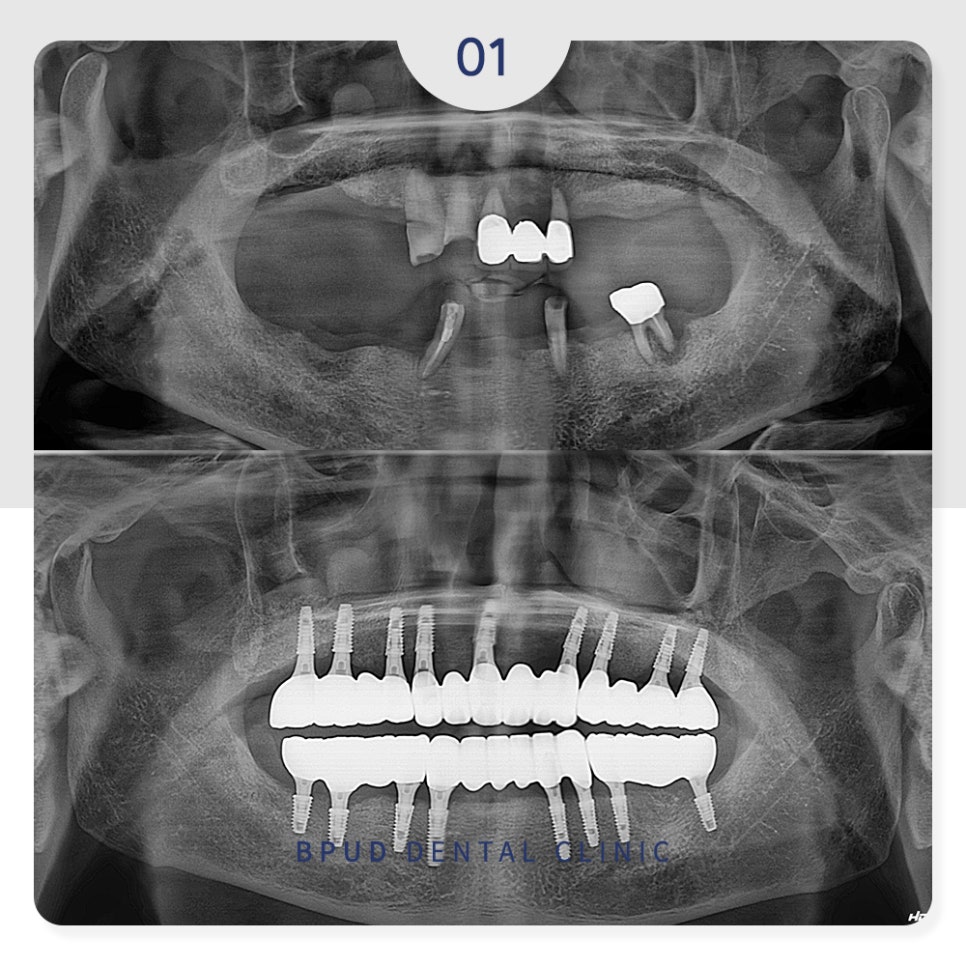

오늘은 남아 있는 치아가 거의 없어

위, 아래 전악 임플란트를 진행하신

환자분을 소개해 드리도록 하겠습니다.

구강 내 치아가 거의 없어

식사도 잘 못하셔서 불편하시며

남아 있는 치아들도 예후가 좋지 않아

모두 발치한 후 부평역치과 전체임플란트를

진행하시기로 계획을 수립하였습니다.

자연치와 동일하게 위, 아래 각각 14개씩

28개 치아를 제작하기로 하고

양쪽 위쪽은 잇몸뼈가 부족한 부위

상악동을 들어 올려 치조골 이식을 진행하는

상악동거상술을 동반하여

임플란트는 각각 9개, 8개를 식립하였습니다.

아래쪽도 잇몸뼈가 부족한 부분은

뼈이식을 동반한 식립을 진행하였습니다.

식립 후 임시 틀니를 제작해 드렸으며

아래쪽은 약 3개월 후

최종 보철물을 완성하였습니다.

위쪽은 난이도가 높은 상악동 거상술을

시행하였으므로 1개월 정도 더 기다려준 뒤

최종 보철까지 마무리하였습니다.